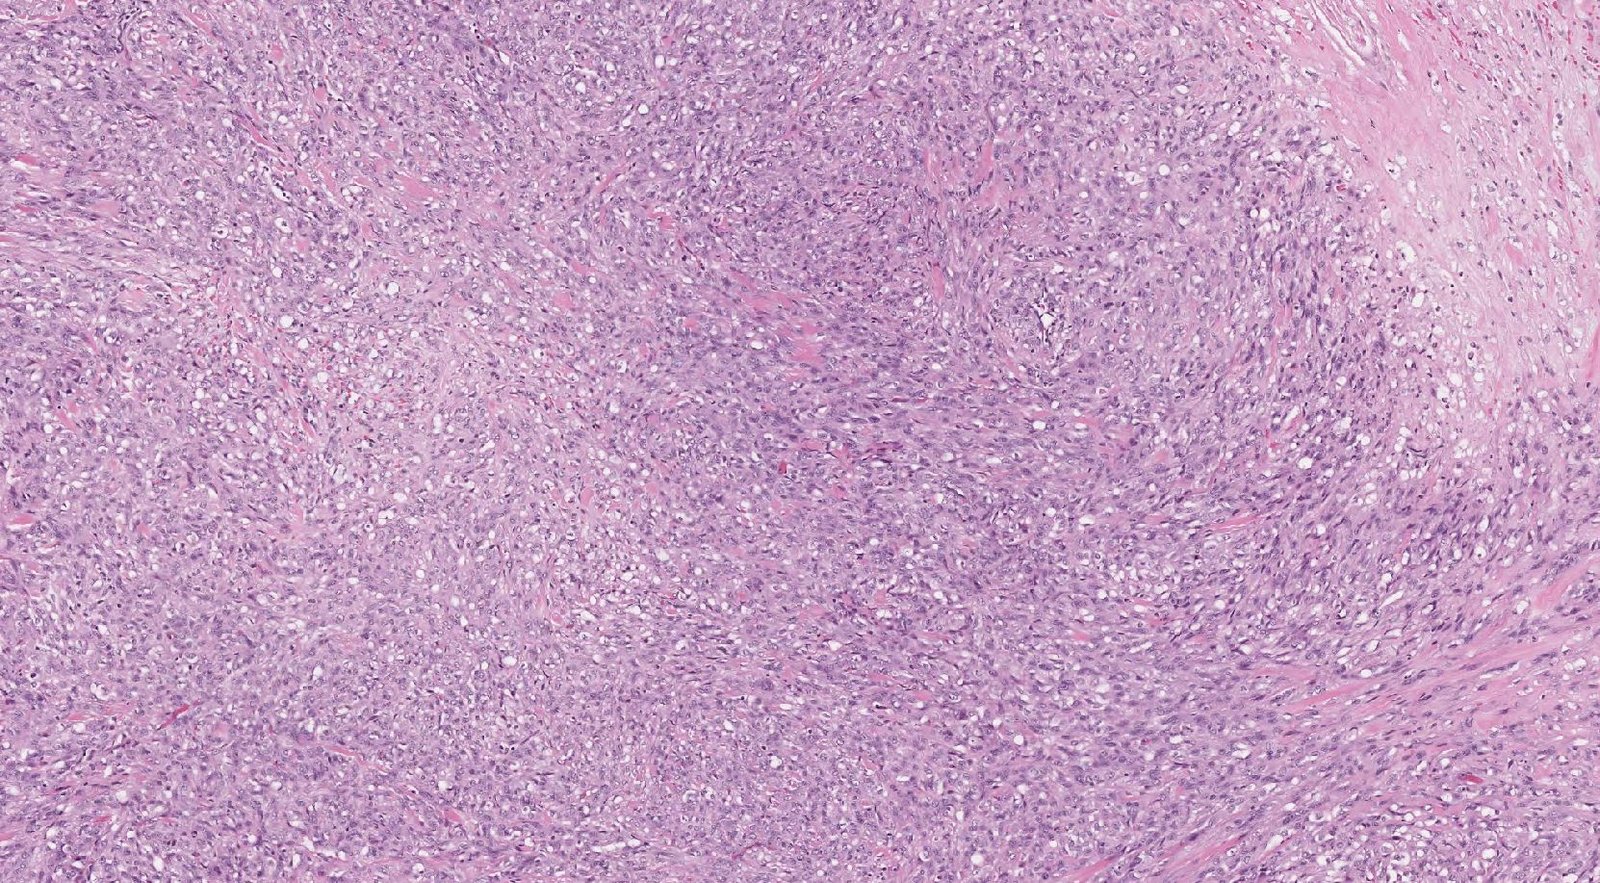

Case: ArmLesion

Final Diagnosis: